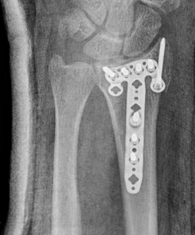

Fragment specific plates

| Volar locking plates | Volar rim plates | Radial styloid plates |

Locking screws act as fixed angle devices Variable angle screws |

Supplementary radial column fixation |